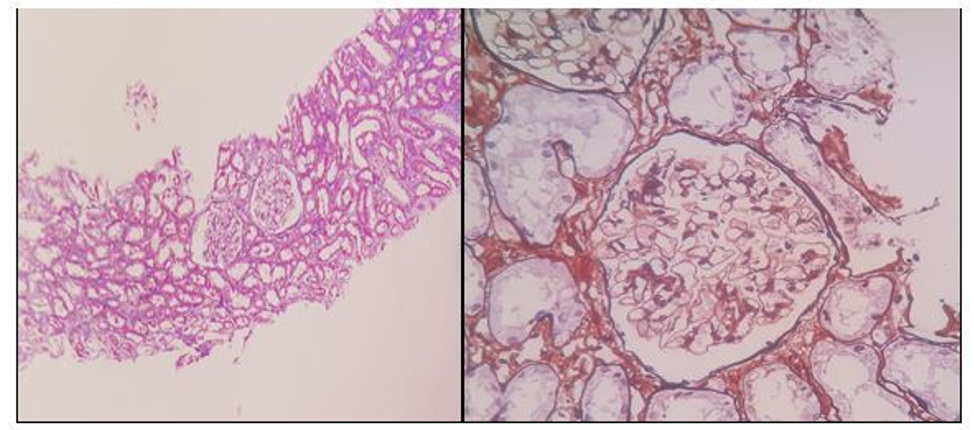

A renal puncture was carried out for biopsy, which was analyzed by a nephropathologist, whose report describes two cylinders that include 23 clusters within the different cuts. None of theme is glob¬ally sclerosed. The walls of the capillary tubes appear to be thin and there is no cellular proliferation. Podocytes are hypertrophied.

In some cases there is extensive fibrosis that extends to the hila. The thioflavin image resulted negative in this material. Minimum focus of tubular atrophy and interstitial fibrosis. The tubules signal light dilatation and a strong irregular vacuolization of the lining epithelium. Vessels with no peculiarities. Inmunohistochemistry: IgG, IgA negative. IgM positive intensity +/++++ focal mesangial and segmental. C3, C1q negative fibrinogen. Kappa and lambada negative. Diagnosis: Morphological findings possibly connected to an MCD. Acute tubular injury (Picture 1a-b, 2a-b).

PICTURES 1a-1b: Periodic Acid-Schiff 200X. Glomerulus without significant histological alterations.

PICTURE 2a-2b: Masson Trichromic Staining 40X. Tubules with vacuolyzation of the lining epithelium. 2b.Silver Methenamine Stain 200X. Thin capillary walls, without deposits or hypercellularity.